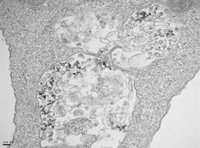

Organoide de colon generado a partir de tumores de ratón.

Organoide de colon generado a partir de tumores de ratón. - PILAR FAJARDO / CNB-CSIC

Cuenda y Juan José Sanz-Ezquerro, investigador del CNB-CSIC, apuntan que el abordaje en esta investigación ha sido "integral". "Pues hemos utilizado muestras humanas de plasma sanguíneo, se han analizado diferentes bases de datos de ARNm de pacientes humanos y hemos generado órganos miniaturizados u organoides derivados de tumores de pacientes, en colaboración con un equipo del Instituto de Investigaciones Biomédicas Alberto Sols (IIB-CSIC-UAM)", añaden.